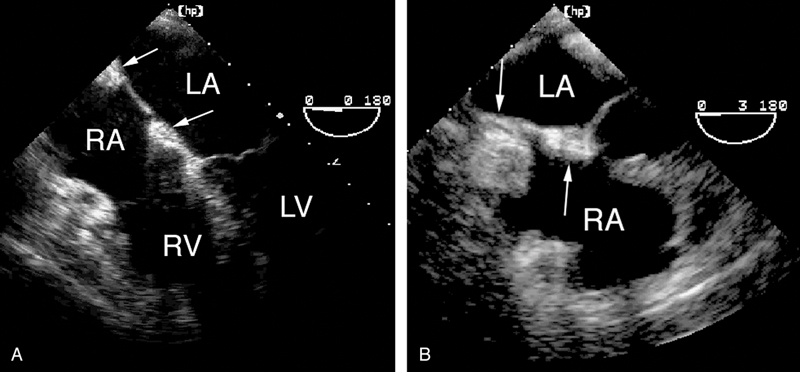

فحوصات تشخيصية لبعض امراض القلب والشرايين التاجية